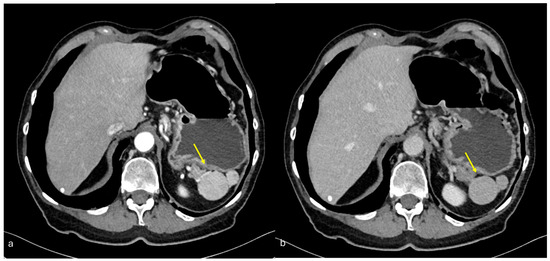

- Nodular pattern: nodules with a diameter > 5 mm (Figure 2a);

- “Omental cake”: nodular thickening of the omentum (Figure 2b);